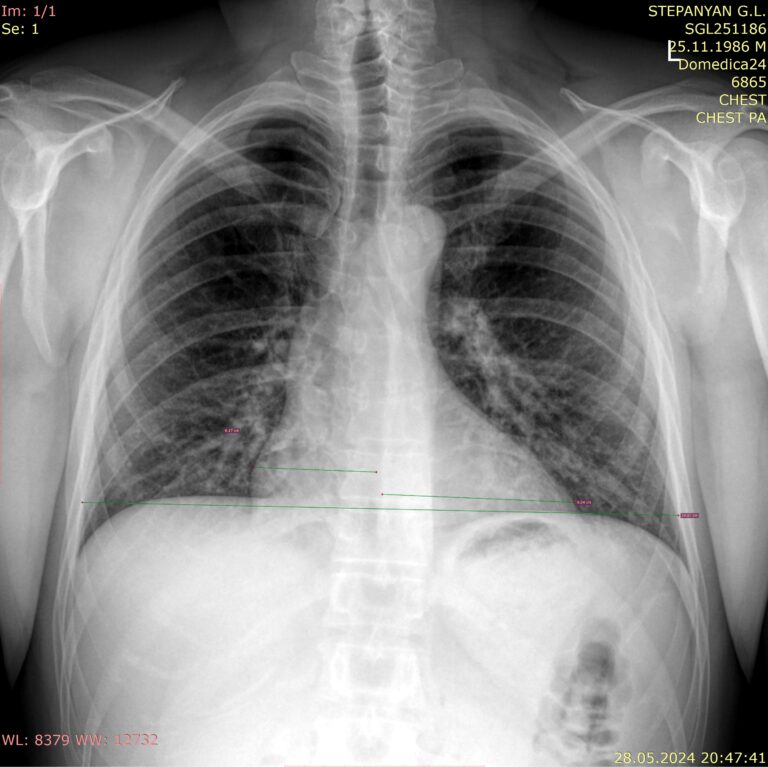

При различных сердечно-легочных заболеваниях сердцу приходится больше и чаще сокращаться, из-за чего его размеры увеличиваются. Эти изменения определяются по рентгеновскому снимку с помощью кардиоторакального индекса (КТИ) и представляют собой отношение поперечника сердца к поперечнику грудной клетки. У здоровых людей данный индекс не превышает 50%, значение от 55% и выше говорят о хронической сердечной патологии.

Кардиоторакальный индекс пишется в процентах.